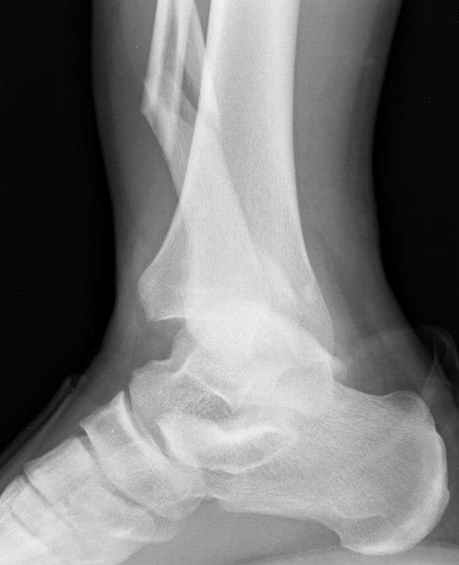

>На сделанных у нас снимках видно, что не все благополучно...

Неравномерность суставной щели может быть связана с разрывом глубокой порции дельтовидной связки и ротацией м/берцовой кости за счет поврежденных структур синдесмоза(репозиция ее на уровне перелома как-будто удовлетворительная).

По моему мнению,ассиметрия суставной щели обусловлена импрессией медиальной части суставной поверхности б/б кости. Да, позиционный винт здесь не лишен, но через 4 недели целесообразность его проведения сомнительна, брейс, ограничение осевой нагрузки достаточно.Есть еще деонтологические аспекты повторной операции, не все так плохо выполнено предыдущим доктором!

Импрессия медиальной части суставной поверхности бывает при супинационном механизме перелома лодыжек (тип А по классификации АО). Здесь механизм пронациия+наружная ротация (тип С, синдесмоз и межкостная мебрана повреждены),

перелом медиальной лодыжки отрывной, при этом в 20-30% бывает повреждение дельтовидной связки.

Клиновидность щели сустава следствие повреждения дельты, невосстановления длины малоберцовой или (хотел сказать "установки в гипсе", но оного, вроде,

нет)? Устранить бы причину. А равно как и тенденцию" к наружному подвывиху. Чрескостный остеосинтез - метод выбора.

Мое мнение, что никакой ротации малоберцовой кости здесь нет и синдесмоз тоже впорядке. Все дело в некачественно репозиции медиального мыщелка. Скорее всего его или немного ротировали при операции или сместили латерально. Более склонен ко второму варианту.

Расширенная медиальная щель более чем на 4 мм и укорочение малоберцовой более чем 2 мм, а перелом заднего края большеберцовой смещения более 2мм с вовлечением 30% поверхности сустава, считается отходом от нормы голеностопного сустава, и подлежит к оперативному вмещательству.